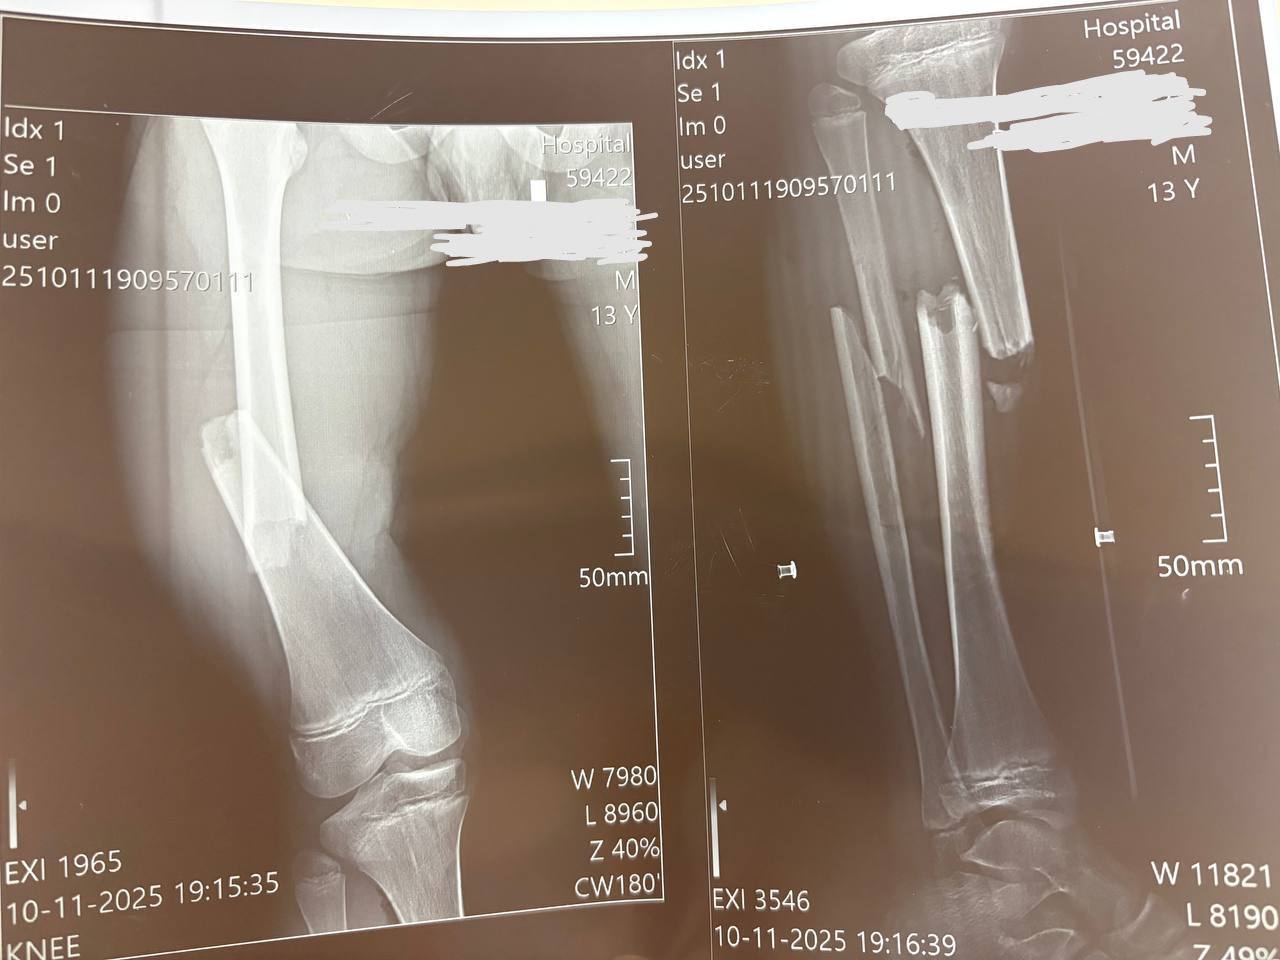

Наслідки падіння для 13-річного Максима – перелом стегнової кістки зі зміщенням і кісток гомілки.«Переломи дуже серйозні, – каже дитячий ортопед-травматолог Богдан Петерчук. – Попри це, завдяки інтрамедулярному остеосинтезу через два дні після операції Максим вже рухає ногою та швидко реабілітується. Оперативне втручання ми зробили через невеликі розрізи на стегні та гомілці».